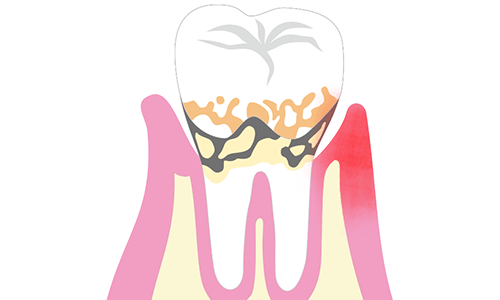

歯周病とは、歯周組織が歯垢(プラーク)に含まれている歯周病菌(細菌)に感染し、歯肉(歯茎)が腫れたり、出血したり、最終的には歯が抜けてしまうなど、日本人が歯を失うもっとも大きな原因のひとつとなっています。

歯周ポケットとは

歯ブラシや歯磨き粉のテレビCM等で「歯周ポケット」という言葉を聞いたことはありませんか?歯周ポケットとは、歯と歯茎の境目の溝のことです。

歯は、歯茎とぴったりつながっているように見えますが、実際は歯と歯茎の間は隙間があります。

その隙間が2mm以下なら良いのですが、深い溝になっていくと、口の中に汚れが溜まりやすくなり、歯周病が進行していきます。

深さは健康な歯茎で1〜2mm、中程度の歯周炎があると3〜5mm、歯周病が進行した場合は6mm以上になることがあります。